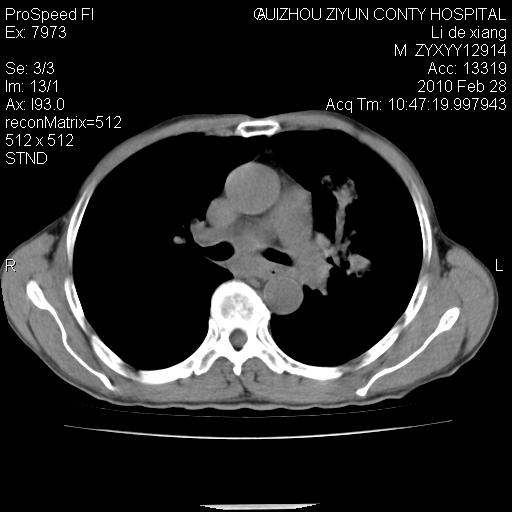

标题: CT24776:男 71Y 咳嗽咳痰胸痛两月,伴声音嘶哑。 [打印本页]

标题: CT24776:男 71Y 咳嗽咳痰胸痛两月,伴声音嘶哑。

左侧中央型肺癌伴左肺上叶阻塞性肺炎及节段性不张可能性大,建议纤支镜检查!

左侧中央型肺癌伴左肺上叶阻塞性肺炎及节段性不张可能性大,建议纤支镜检查!纵隔淋巴结转移.

左侧中央型肺癌伴左肺上叶阻塞性肺炎及纵隔淋巴结转移。

左肺门部肿块,伴左上肺斑块影,周边模糊,支持左肺中央型肺癌伴节段性不张及阻塞性肺炎,结合支气管镜检查。

左上叶支气管狭窄,阻塞性病变,肺门肿块,纵隔及肺门淋巴结增大,中央性肺癌

左肺中央型肺癌并阻塞性改变、纵膈 淋巴结转移

左侧中央型肺癌伴左肺上叶阻塞性肺炎及纵隔淋巴结转移

支持 左肺中央型肺癌伴左肺上叶阻塞性肺炎,纵隔淋巴结转移。